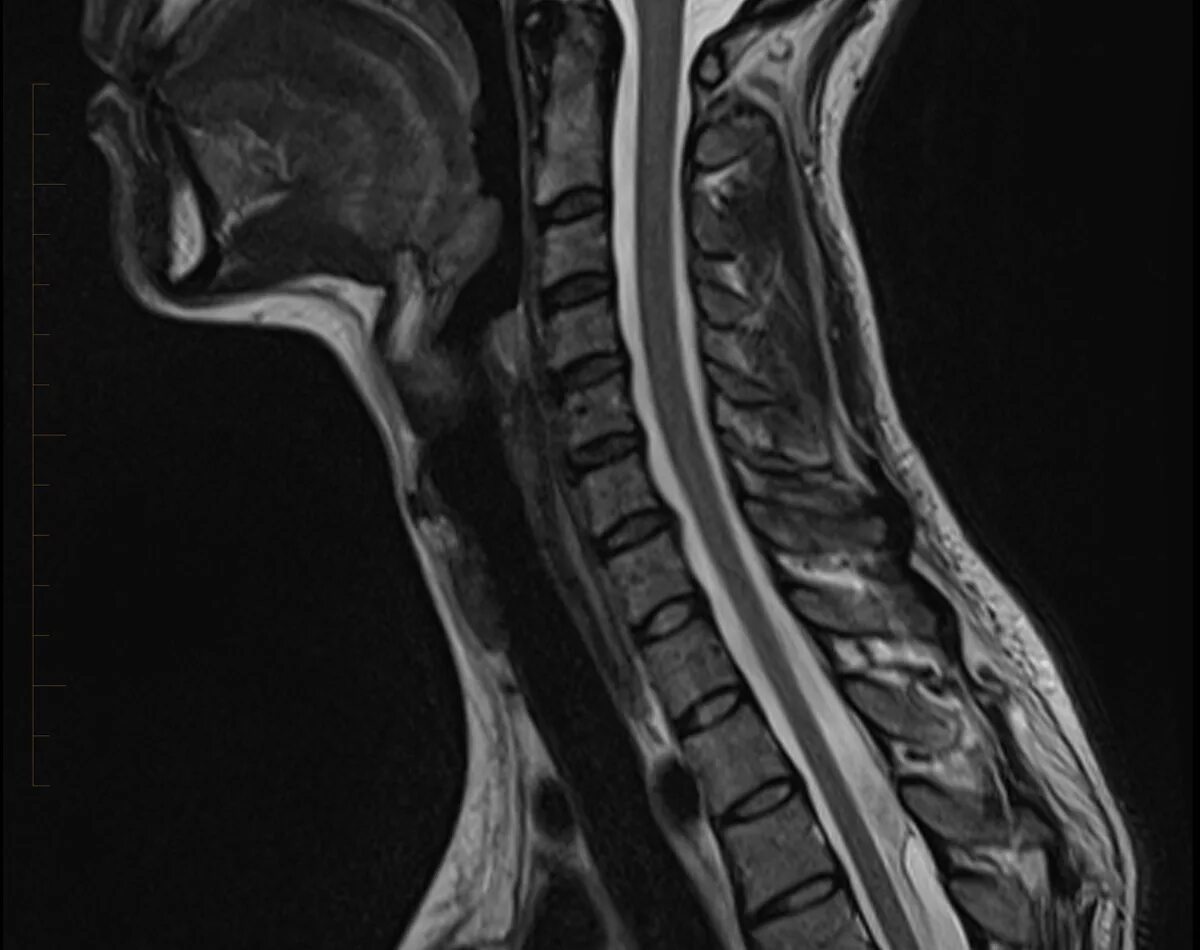

Spine mri